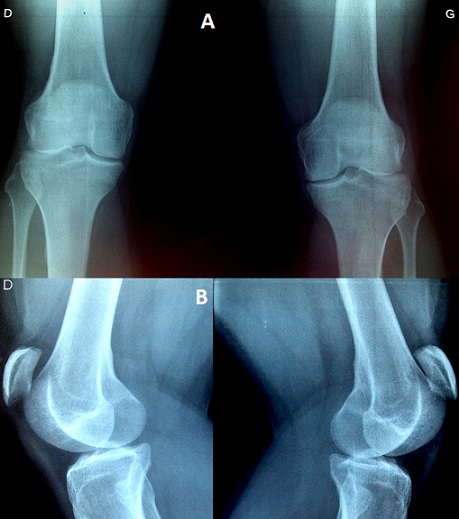

Bilateral patellar tendon rupture is usually associated with systemic immunologic or connective tissue disease, steroid use, fluoroquinolone antibiotic use, or renal disease. Amongst the spontaneous cases, bilateral ruptures are exceedingly rare and have only been documented in a few case reports. We present a case of bilateral midsubstance patellar tendon ruptures along from a fall from a standing height in a 34-year-old otherwise healthy adult without any predisposing conditions, diagnosed in clinical examination with a little extension deficit, and confirmed in plain radiographs showing a bilateral patella alta (A, B). Most patients that sustain a tendon rupture have risk factors for tendinopathy including chronic renal disease, systemic lupus erythematosus, rheumatoid arthritis, or exposure to medications (such as fluoroquinolones or corticosteroids). To the best of our knowledge, this condition is often misdiagnosed. Despite the rarity of cases in patient's without systemic disease, emergency physicians must maintain a high index of suspicion of a knee extensor injury in a patient who is unable to actively extend the knees associated with patella alta.